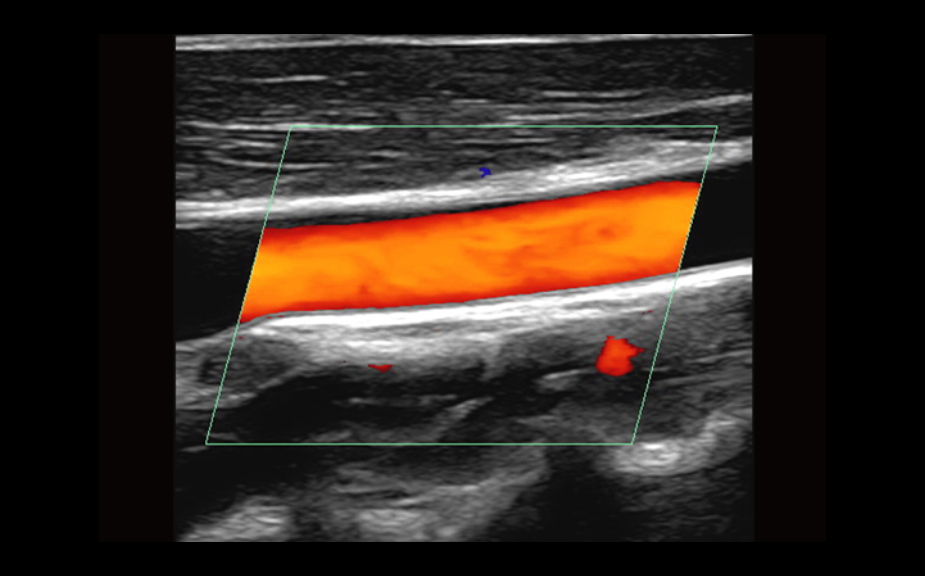

Equipado con software patentado con base en tecnolog├Ła ZONE?Sonography? (ZST),?el Z.One PRO proporciona toma de im├Īgenes Doppler y Modo-B detalladas ├│ptimamente para pacientes, sin importar la complexi├│n del cuerpo, ayudando a asegurar un diagn├│stico confiable.

- Insuperable calidad de imagen en todas las aplicaciones

El Z.One PRO est├Ī dise?ado bas├Īndose en ZONE Sonography Technology, una arquitectura de formaci├│n de im├Īgenes innovadora y registrada que adquiere y procesa informaci├│n ac├║stica hasta 10 veces m├Īs r├Īpido que los m├®todos de formaci├│n de haces convencionales.